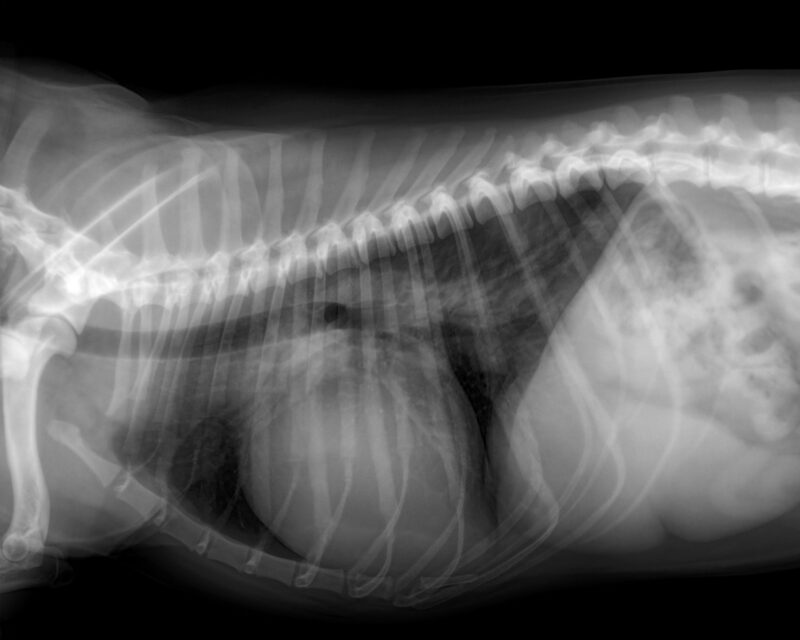

Auf den Röntgenbildern bestätigt sich das, was bei der Untersuchung schon verdächtig war: Das Herz ist deutlich zu groß und man kann ein Lungenödem, also gestaute Gefäße sowie Wasser in der Lunge erkennen.